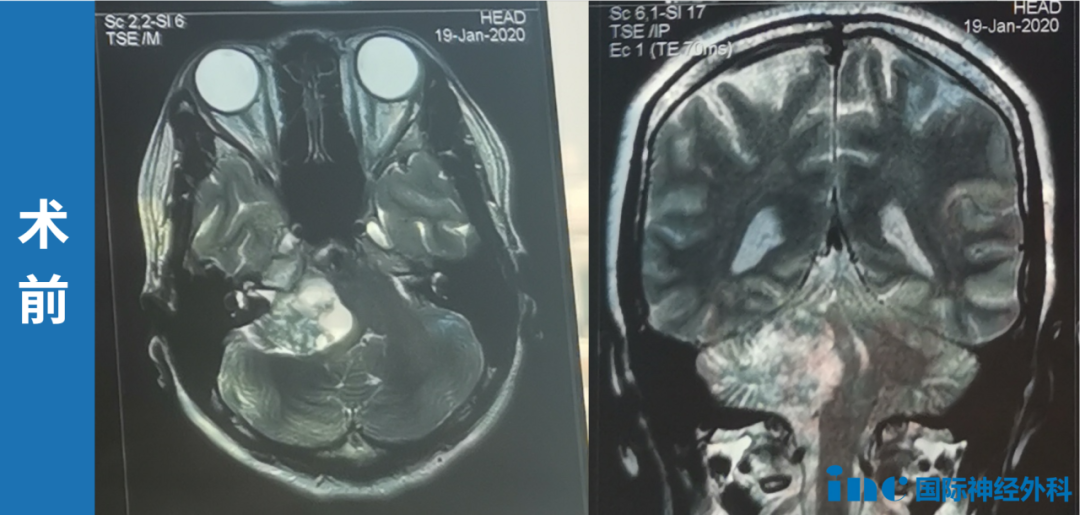

而在2020年1月19日的详细MR检查显示:右侧桥小脑角区有一个约37mm×27mm的病灶,脑桥、四脑室及右侧小脑半球受推压。初步诊断指向右脑桥小脑角肿瘤,疑似神经鞘瘤,并怀疑可能来源于掌管听觉的蜗神经。这个诊断,意味着她可能需要面对一场听神经、面神经功能可能受损的高风险手术。